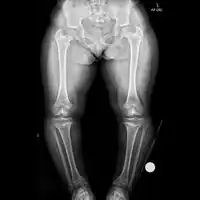

Radiologic findings

A skeletal survey is useful to confirm the diagnosis of achondroplasia. The skull is large, with a narrow foramen magnum, and relatively small skull base. The vertebral bodies are short and flattened with relatively large intervertebral disk height, and there is congenitally narrowed spinal canal. The iliac wings are small and squared, with a narrow sciatic notch and horizontal acetabular roof.[15][16] The tubular bones are short and thick with metaphyseal cupping and flaring and irregular growth plates.[15] Fibular overgrowth is present. The hand is broad with short metacarpals and phalanges, and a trident configuration. The ribs are short with cupped anterior ends.[15] If the radiographic features are not classic, a search for a different diagnosis should be entertained. Because of the extremely deformed bone structure, people with achondroplasia are often "double jointed". The diagnosis can be made by fetal ultrasound by progressive discordance between the femur length and biparietal diameter by age. The trident hand configuration can be seen if the fingers are fully extended.